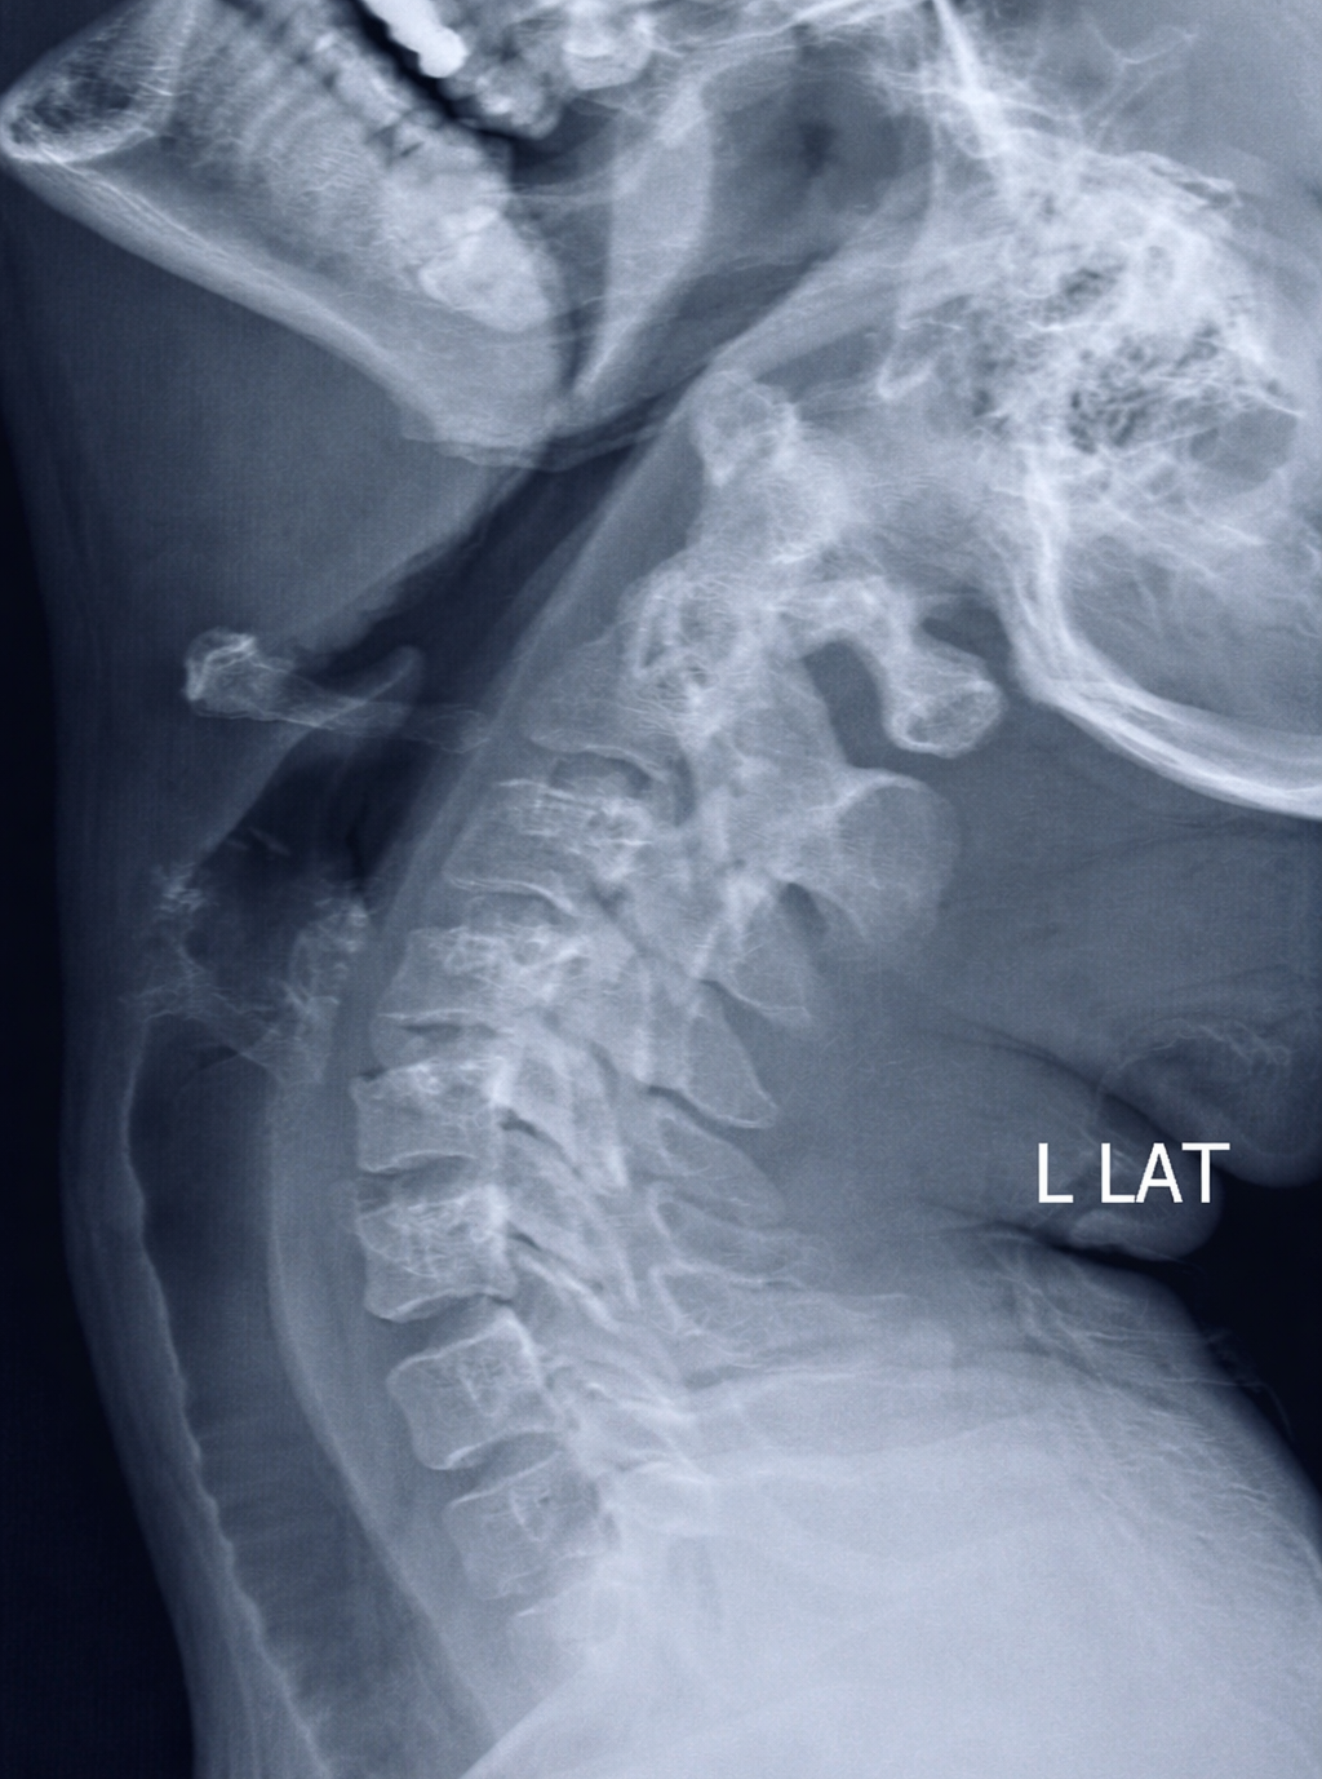

Spinal Instability & Symptomatic Disk, Joints and Ligaments

Platform identifies imaging findings related to spinal instability, symptomatic disc abnormalities, facet joint changes, and ligamentous injuries for physician review and clinical correlation.

AI-Driven Clinical Insight

Multi-Level Spine Analysis Example

Imaging shows findings consistent with instability at L4/5 and L5/S1 following prior percutaneous disc procedure. Board-certified physician review recommended for treatment planning.